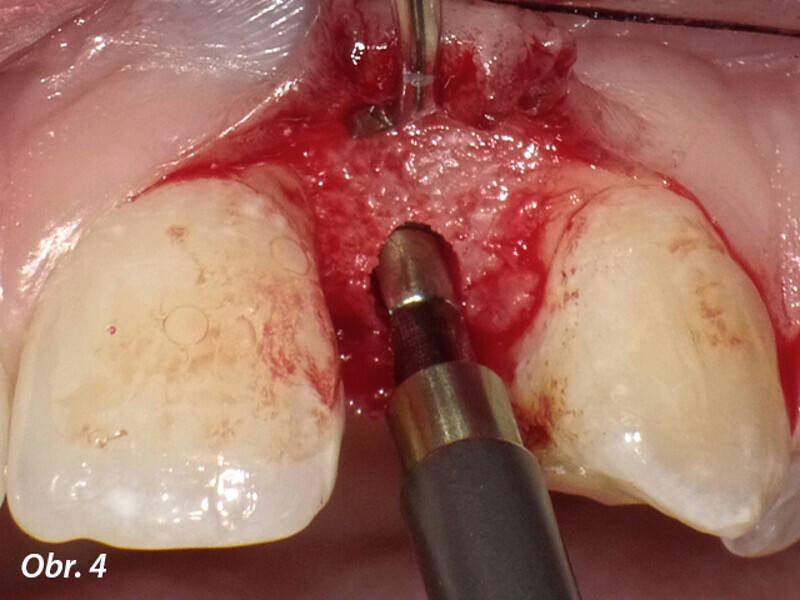

Aproximální rozšíření mezi kořeny zubů za účelem zavedení úzkého implantátu